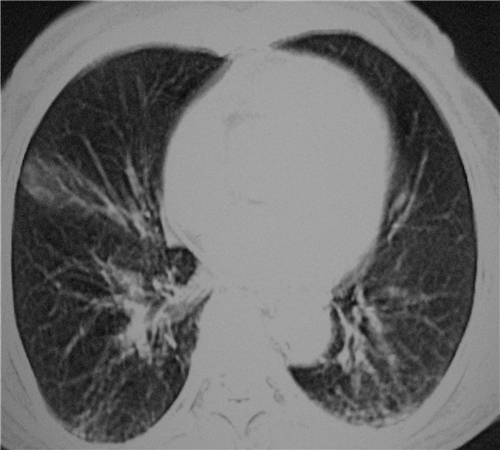

标题: CT26849:女67岁反复胸痛两天余,临床考虑夹层。 [打印本页]

标题: CT26849:女67岁反复胸痛两天余,临床考虑夹层。

右肺感染,未见夹层。

既然考虑夹层,建议强化!另:右下肺感染!

1)右肺感染性病变。2)建议行ct增强扫描或mri检查排除主动脉夹层。

双下肺感染,右侧显著。有无夹层,增强扫描后再诊断。

1. 感染性病变,2.未见夹层,3.食道未见异常。